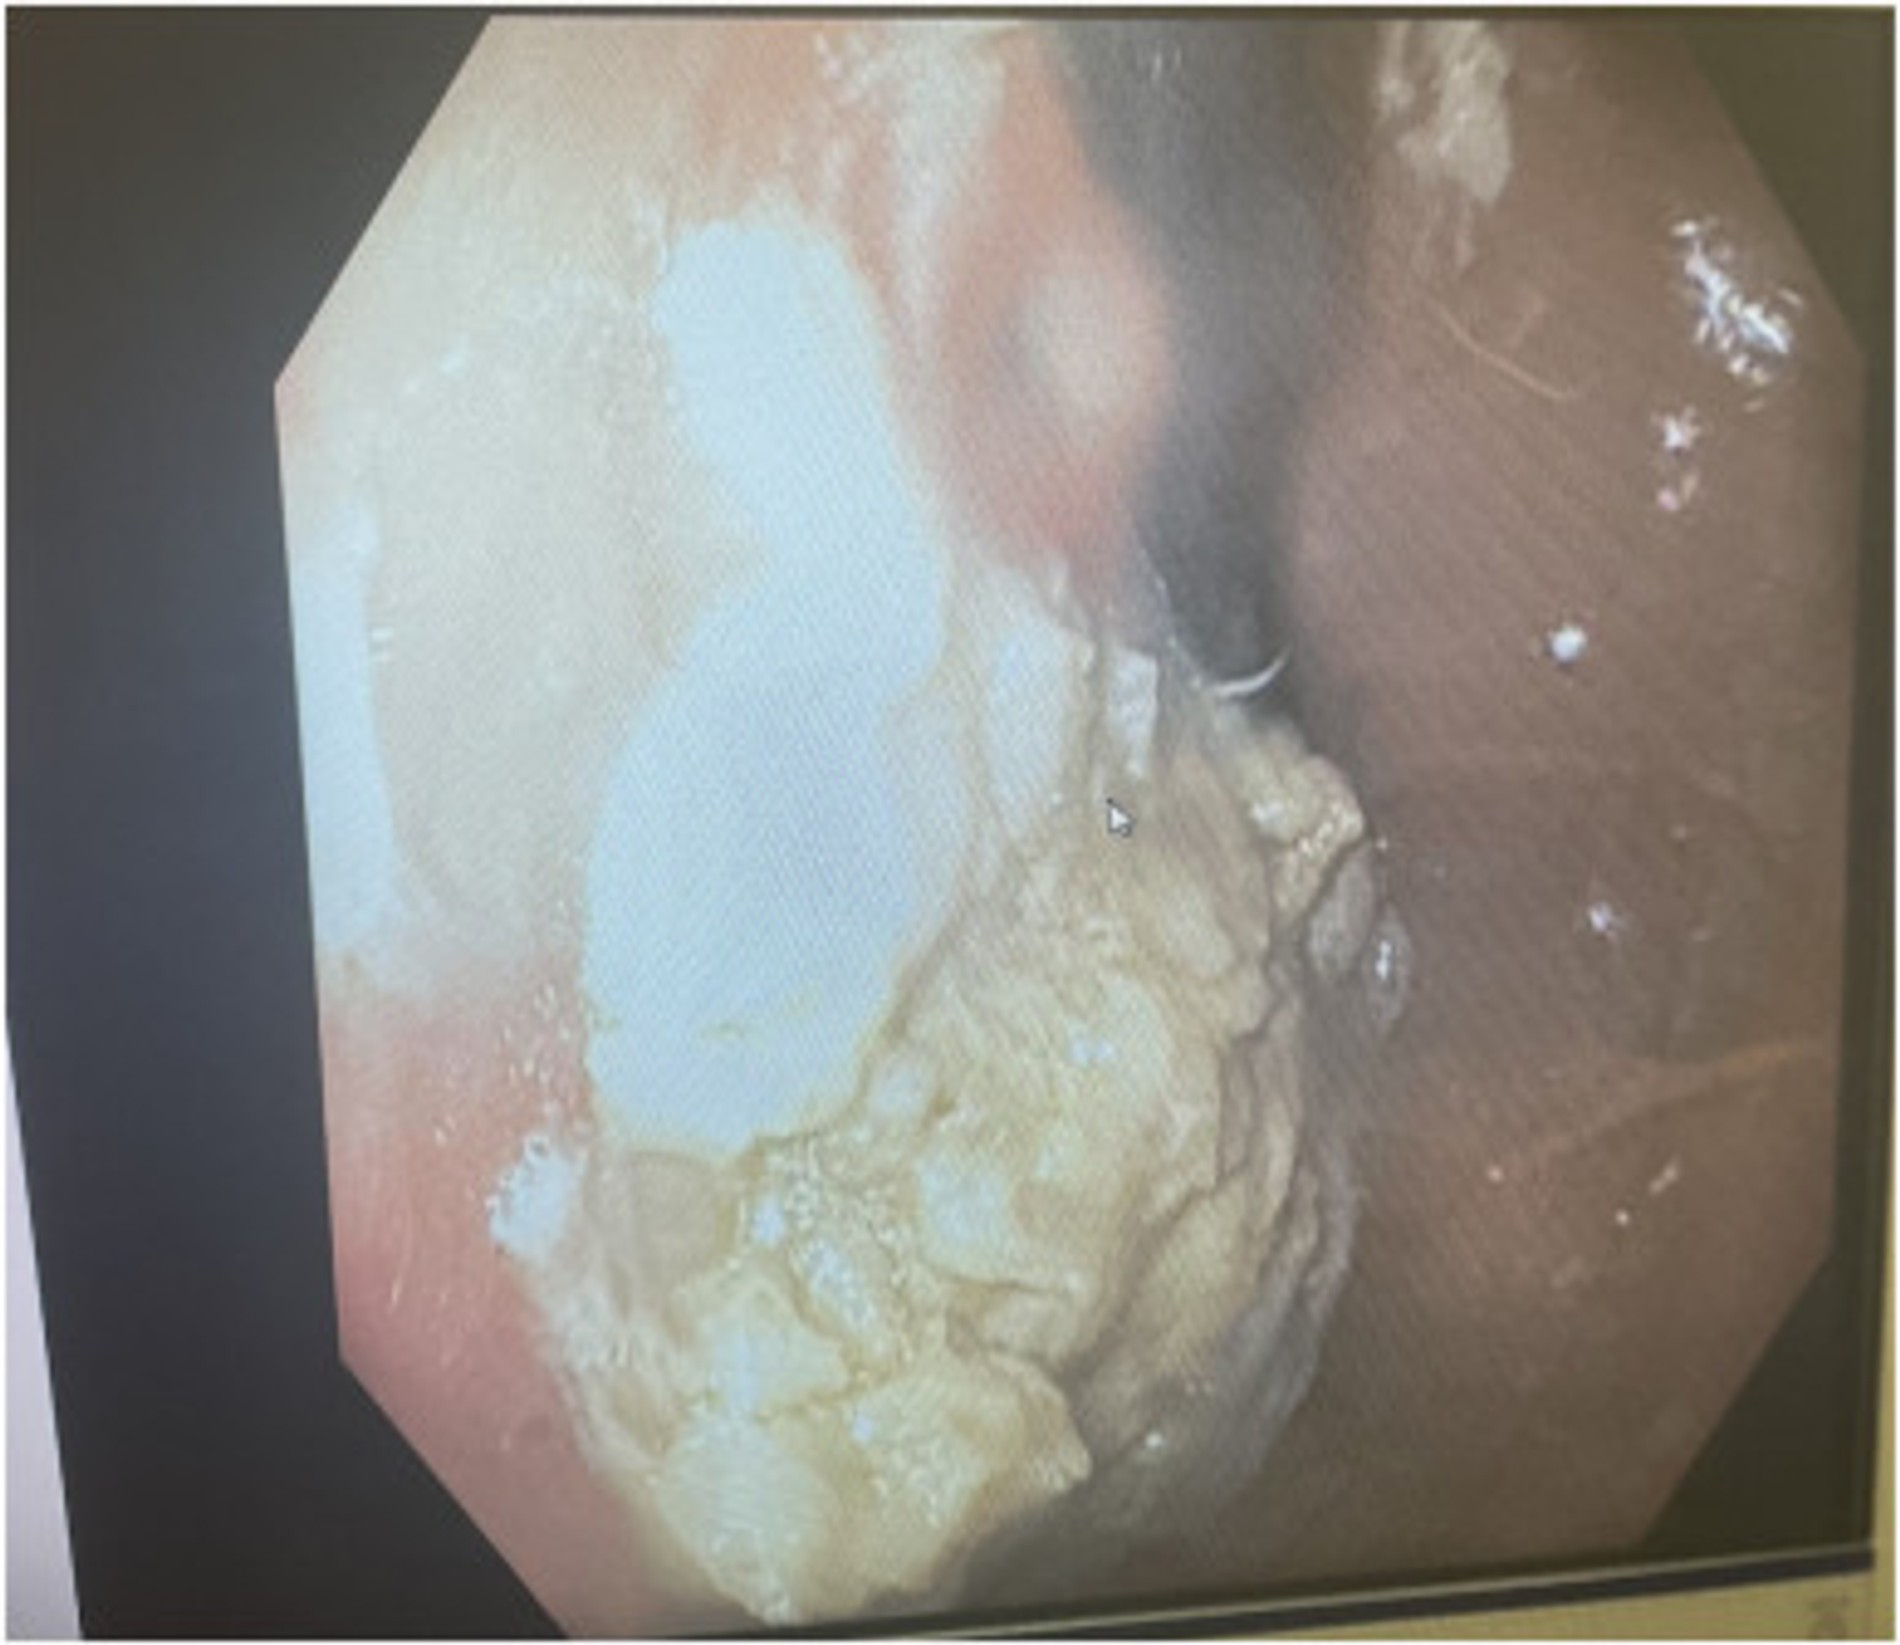

Узнав, сколько жвачки съел ребенок, медики решили сразу сделать ему рентген, КТ и ЭГДС. В итоге обследование выявило в желудке огромный безоар (инородное тело) из жевательной резинки. По данным врачей, он заполнил примерно 25% желудка юного пациента. Растворить массу жвачки оказалось невозможно, а от хирургического вмешательства отказались из-за отсутствия опасности для других органов. Лучшим вариантом врачи посчитали постепенно удалить образовавшийся безоар с помощью эзофагоскопа через рот. В итоге все завершилось успешно и мальчика вскоре выписали.